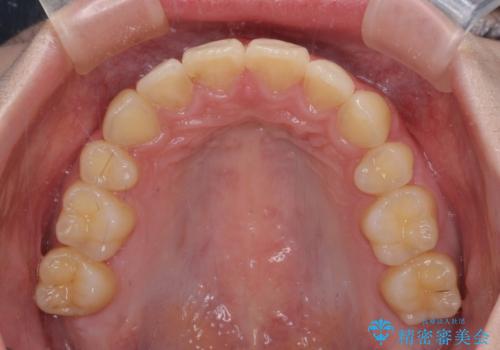

- 口元の突出感を気にして来院された患者様です。

左側の咬み合わせと上下正中の位置をコントロールするために時間がかかりましたが、事前に思い描いた通りの歯列に整い、患者様には大変満足していただきました。